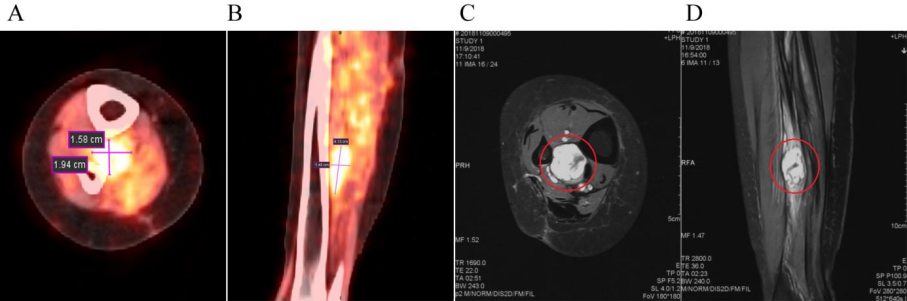

病例二:患者,女,55岁。病史:右小腿脂肪肉瘤,曾于2014年11月17日和2016年3月30日接受两次广泛切除术。第二次术后于2016年5月接受辅助放疗(总剂量50.4Gy/28次,后续加量10Gy/5次)。2018年11月1日,PET-CT和MRI(图1)显示肿瘤复发,病灶位于右胫腓骨中间隙,大小约4.2×2.0 cm。临床诊断为右小腿脂肪肉瘤复发。2018年11月,患者接受重(碳)离子治疗,治疗方案为:总剂量64Gy(RBE),分16次,在28天内完成(每周一至周五,每日一次),照射野设计采用两野计划(水平野和垂直野,见图2)。

图1. 治疗前影像学检查

(A) PET/CT轴位图像:可见高SUV摄取灶。(B) PET/CT矢状位图像:T2WI呈高信号。(C) MRI轴位和 (D) MRI矢状位图像。